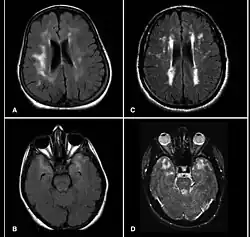

Axiale FLAIR (A, B, C) und T2-gewichtete Magnetresonanztomographien von CADASIL-Patienten. A und B sind asymptomatische Patienten mit Depression. In B sind Läsionen des Temporallappens nachweisbar. In A und D finden sich diffuse ischämische Veränderungen der weißen Substanz um die Hirnventrikel (periventrikulär) sowie multiple kleine Infarkte (Status lacunaris) in Thalamus, Pons und Basalganglien.

In der Magnetresonanztomographie des Gehirns finden sich in T2-gewichteten Aufnahmen Signalverstärkungen in der weißen Substanz, typischerweise insbesondere auch temporal.